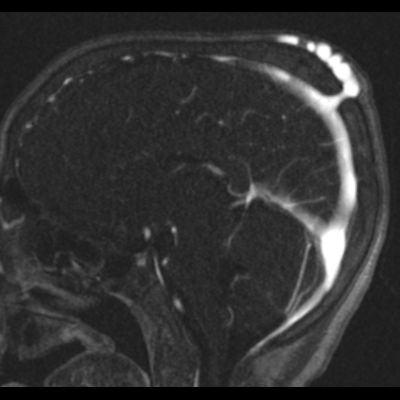

2. B) Kontrastlı MR venografide orta hatta cilt altı dilate (oklar), tortiyoze emisserian vaskuler yapıların superior sagital sinus ile ilişkisi ve devamlılığı (ok) izlenmektedir.

6. En tanımlayıcı görüntüleme yöntemi MR venografidir.

7. İntrakraniyal ve ekstrakraniyal venöz yapıların ilişkisi net şekilde gösterilir.

8. Lezyonun süperior sagittal sinüs veya diğer venöz sinüslerle bağlantısı doğrulanır.